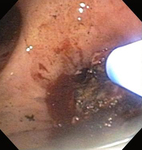

Post-lung transplant anastomotic bronchial stenosis: electrocautery radial incision

From the collections of Jose Fernando Santacruz MD, FCCP, DAABIP and Erik Folch MD, MSc; used with permission